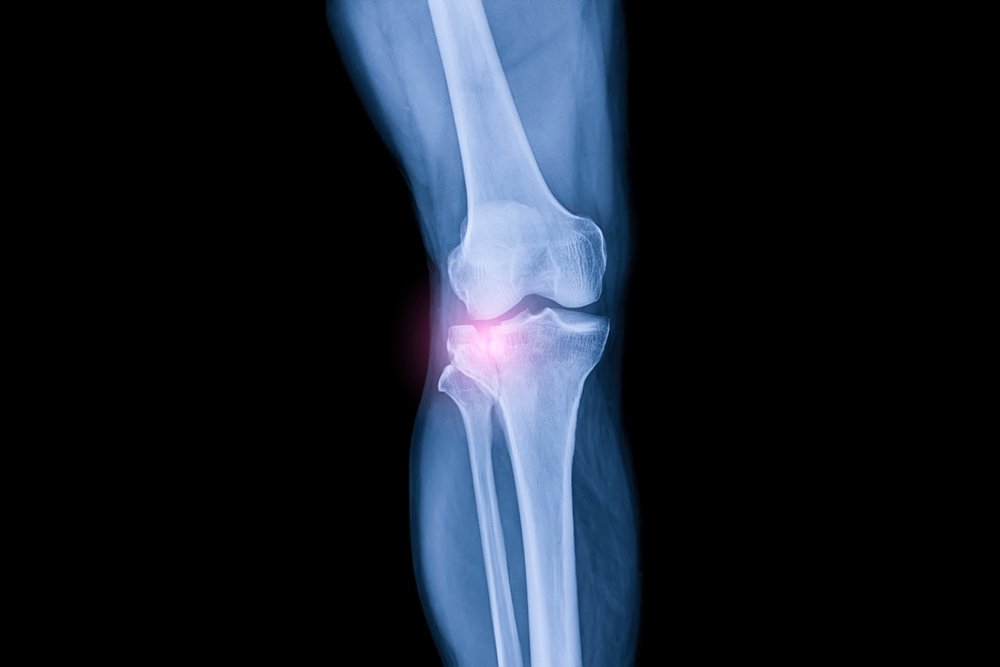

Знаете ли вы, что почти каждый четвертый взрослый в США страдает хронической болью в суставах, при этом колено является одной из наиболее часто поражаемых областей?Боль в колене может существенно повлиять на вашу повседневную жизнь, лишая вас возможности наслаждаться занятиями, которые вы когда-то любили, и ограничивая вашу подвижность.

К счастью, достижения в области регенерации коленного хряща дают новую надежду тем, кто борется с болью в суставах.